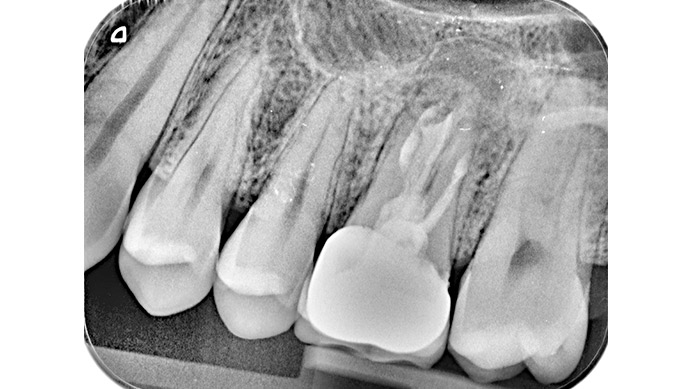

Ian es un paciente que nos cuenta su experiencia tras una intervención de cirugía periapical. Ian vino a la clínica dental IDIM con molestias en una muela superior que en el estudio radiográfico se vio que presentaba infección a causa del fracaso de una endodoncia.

Se decidió realizar una cirugía periapical para eliminar la infección y sellar las raíces con un empaste para evitar que volviera a tener problemas. Gracias a esta efectiva intervención Ian conserva su muela, lo cual es preferible, siempre que se puede, a tener que extraerla y sustituirla con un implante dental.